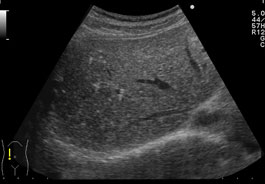

過誤腫は適切な検査がなければ診断が困難です。これらの増殖は癌性腫瘍に似ている可能性があるため、悪性でないことを確認するために検査する必要があります。

これらの良性腫瘍と癌性腫瘍を区別するために医師が使用する検査や手順には、次のようなものがあります。